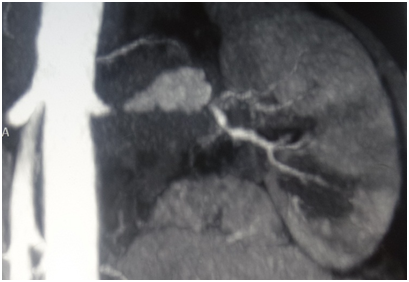

After 4months of antiviral treatment his CRP was now elevated up to 98mg/L, he developed mild leukocytosis (WBC 10.4x109/L), his thrombocytosis persisted, and his serum creatinine raised to 150µmol/L. Ultrasound now found left kidney shrinkage with renal blood flow reduction and left epididymis enlargement; right kidney and right epididymis were otherwise normal. He was suspected with left testicle neoplasm; however his LH, FSH, estradiol, progesterone, prolactin, testosterone, ACTH, cortisol, aldosterone, AFP, PSA and free beta HGC were all normal. Antiviral treatment was discontinued, and he underwent contrast-enhanced abdomen CT and CT-angiography, which showed pseudo-aneurism of the left artery, left artery proximal occlusion and reduced left kidney excretory function (Figures 1 & 2). Eleven months after his first presentation he was referred to our hospital and admitted to the vascular surgery.

Figure 1 CT scan, showing left renal artery pseudo-aneurism and proximal occlusion.

Figure 2 CT scan, showing blood flow reduction of the left kidney.